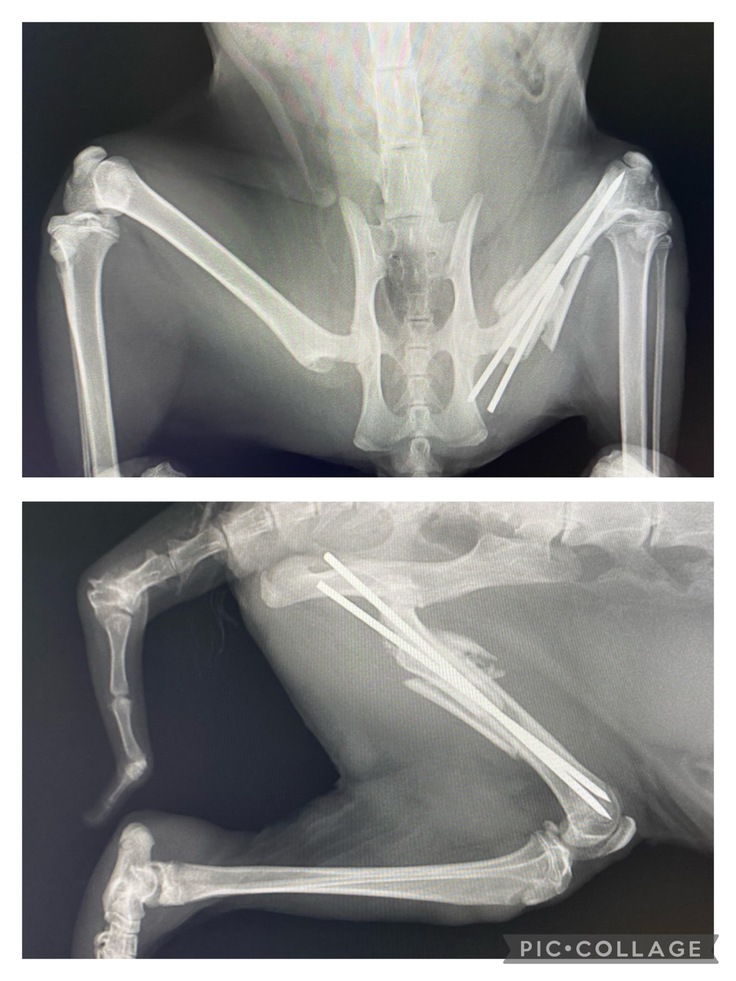

骨折治療のためワイヤーを挿入する手術を行いました。

併せて、去勢手術も行っています。

レントゲン写真を撮ると、骨折した部位が縦に割れていることがわかりました。

また、ワイヤーが左のしっぽ脇辺りから皮膚を突き破って外に貫通…

皮膚の外に飛び出したワイヤーを切除、周辺の皮膚を縫合する処置を行いました。

転院先の動物病院で、ワイヤーを抜く手術を受けました。

さらに、前回ワイヤーが貫通した周りの皮膚が壊死していたため、壊死した皮膚の除去も併せて行いました。